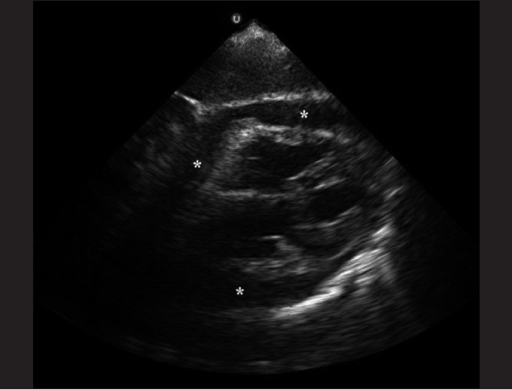

File:Pericardial Effusion.png

Pericardial effusion

Acquired from: OPENi - An Open Access Biomedical Search EngineAn Open Access Biomedical Image Search Engine